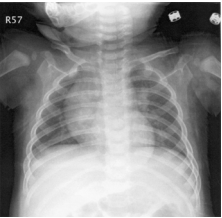

89 一個 6 個月大的嬰兒因為咳嗽 3 天就診,肺部與心臟 聽診正常,胸部 X 光片如圖所示。下列那一項最符合 胸部 X 光所見?

(A) Lobar pneumonia (B) Atelectasis of lung (C) Prominent thymus shadow (D) Cardiomegaly